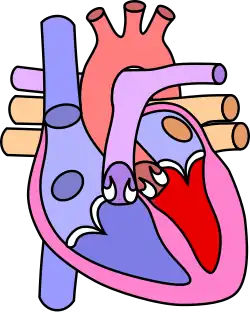

![]() | |

| Diagram of a healthy heart and one with tetralogy of Fallot | |

Tetralogy of Fallot (TOF), formerly known as Steno-Fallot tetralogy,[9] is a congenital heart defect characterized by four specific cardiac defects.[4] Classically, the four defects are:[4]

- Pulmonary stenosis, which is narrowing of the exit from the right ventricle;

- A ventricular septal defect, which is a hole allowing blood to flow between the two ventricles;

- Right ventricular hypertrophy, which is thickening of the right ventricular muscle; and

- an overriding aorta, which is where the aorta expands to allow blood from both ventricles to enter.

Four malformations

"Tetralogy" denotes four parts, here implying the syndrome's four anatomic defects.[2] This is not to be confused with the similarly named teratology, a field of medicine concerned with abnormal development and congenital malformations (including tetralogy of Fallot). Below are the four heart malformations that present together in tetralogy of Fallot:

| Pulmonary Infundibular Stenosis | A narrowing of the right ventricular outflow tract. It can occur at the pulmonary valve (valvular stenosis) or just below the pulmonary valve (infundibular stenosis).[4] Infundibular pulmonic stenosis is mostly caused by the overgrowth of the heart muscle wall (hypertrophy of the septoparietal trabeculae),[42] however, the events leading to the formation of the overriding aorta are also believed to be a cause. The pulmonic stenosis is the major cause of the malformations, with the other associated malformations acting as compensatory mechanisms to the pulmonic stenosis.[43] The degree of stenosis varies between individuals with TOF and is the primary determinant of symptoms and severity. This malformation is infrequently described as sub-pulmonary stenosis or subpulmonary obstruction.[44] |

| Overriding aorta | An aortic valve with biventricular connection, that is, it is situated above the ventricular septal defect and connected to both the right and the left ventricle. The degree to which the aorta is attached to the right ventricle is referred to as its degree of "override." The aortic root can be displaced toward the front (anteriorly) or directly above the septal defect, but it is always abnormally located to the right of the root of the pulmonary artery. The degree of override is extremely variable, with 5–95% of the valve being connected to the right ventricle.[42] |

| Ventricular septal defect (VSD) | A hole between the two bottom chambers (ventricles) of the heart. The defect is centered around the most superior aspect of the ventricular septum (the outlet septum), and in the majority of cases is single and large. In some cases, thickening of the septum (septal hypertrophy) can narrow the margins of the defect.[42] |

| Right ventricular hypertrophy | The right ventricle is more muscular than normal, causing a characteristic boot-shaped (coeur-en-sabot) appearance as seen by chest X-ray. Due to the misarrangement of the external ventricular septum, the right ventricular wall increases in size to deal with the increased obstruction to the right outflow tract. This feature is now generally agreed to be a secondary anomaly, as the level of hypertrophy tends to increase with age.[45] |